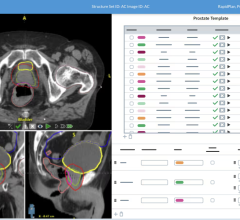

April 7, 2025 — DOSIsoft, a provider of patient-specific imaging and dosimetry software solutions, recently announced ...